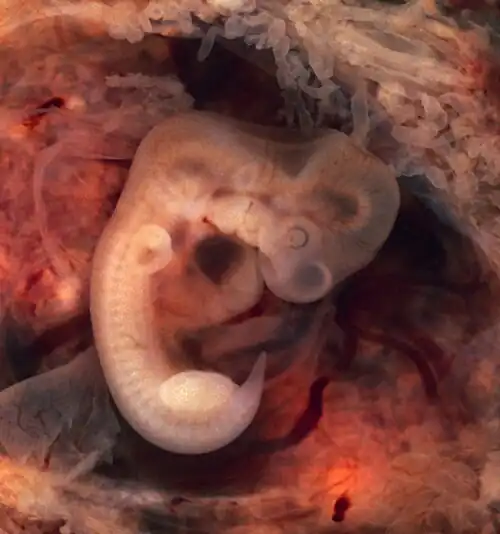

{{cite book}}: CS1 maint: multiple names: authors list (link) - ^ 3D Pregnancy Archived 27 September 2007 at the Wayback Machine (large image of fetus at 4 weeks after fertilization). Retrieved 2007-08-28. A rotatable 3D version of this photo is available here Archived 14 September 2007 at the Wayback Machine, and a sketch is available here Archived 27 September 2007 at the Wayback Machine.

- The embryo measures 4 mm (1⁄8 in) in length and begins to curve into a C shape.

- The embryo measures 8 mm (0.31 in) in length and weighs about 1 gram.[4]

- The embryo measures 13 mm (1⁄2 in) in length.